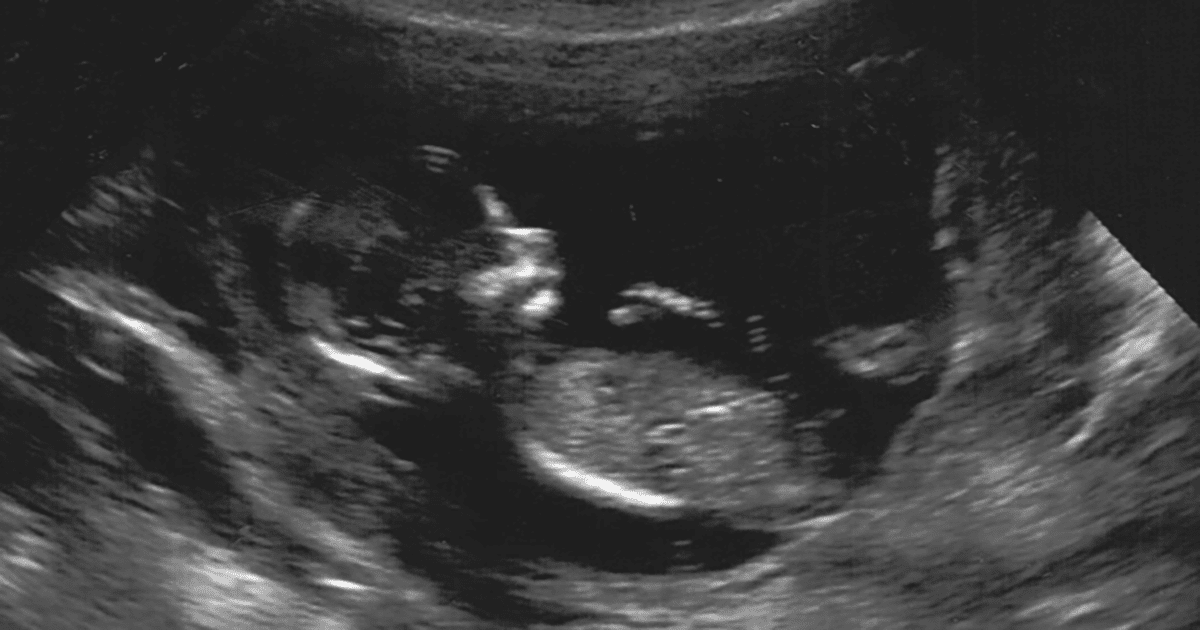

Tijdens je zwangerschap worden er standaard een aantal echo’s gemaakt. Dit is een onderzoek waarbij er met geluidsgolven een beeld wordt gemaakt van uw baby. Dit onderzoek doet geen pijn.

Vanaf 5 weken en 3 dagen zwangerschap klopt het hartje van de baby bij een intacte zwangerschap. Om zeker te weten dat het hartje zichtbaar is op de echo, wordt de eerste echo gedaan met 7 weken zwangerschap. Ook wordt er gekeken of de baby in de baarmoeder groeit. Deze echo wordt niet standaard gedaan, maar alleen op medische indicatie. Echter, Verloskundigenpraktijk PuurBegin biedt deze echo gratis aan.

In principe worden echo gedaan aan de buitenkant van je buik. Hiervoor moet de buik bloot zijn, maar je hoeft je BH en broek niet uit te doen. Er wordt wat gel op de buik gedaan om met het aparaat te kunnen kijken naar de baarmoeder en baby. Omdat de baarmoeder met 8 weken nog heel klein is en achter je schaambot zit, kunnen de geluidsgolven van de ech hier soms niet doorheen. Het lukt dan niet om het hartje van de baby te zien met een echo aan de buitenkant van de buik. Het is belangrijk om het hartje van de baby goed in beeld te krijgen, om te vertellen of de zwangerschap nog intact is. Daarom wordt deze vroege echo altijd via de vagina inwendig gedaan. Een inwendige echo doet geen pijn, maar kan wel een gek gevoel zijn. Als je in het verleden een vervelende ervaring hebt gehad met een inwendig onderzoek of op seksueel gebied, kan een inwendige echo minder prettig zijn. Als het niet gaat, kun je de hand van degene pakken die de echo maakt. Hiermee weten we dat er even pauze moet worden genomen en kunnen we rekening met je houden.

Er wordt tijdens de echo ook gekeken of de baarmoeder een normale vorm heeft en of er geen andere afwijkingen te vinden zijn. Als de zwangerschap niet in de baarmoeder zit maar ergens erbuiten (bijvoorbeeld in de eierstok), blijft de zwangerschap niet intact. Een zwangerschap buiten de baarmoeder kan schadelijk zijn.

Als het hartje bij deze echo niet klopt, kan dit betekenen dat de baby niet meer leeft. Soms kan het ook betekenen dat je korter dan 8 weken zwanger bent en dat de echo misschien te vroeg is gemaakt. De echo wordt dan herhaald na een week om zeker te weten of de baby nog leeft.